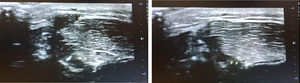

A male adolescent aged 15 years presented with lumps on the lower extremities that have developed progressively over two months. The lesions caused him pain during physical activity and limited his ability to exercise. He was otherwise healthy, with no relevant medical history, and an athlete. The examination at rest revealed three lumps on the right lower limb (Fig. 1) and two on the left, soft to the touch, that were not tender, red or warm, located in the tibialis anterior region. The lumps disappeared upon muscle contraction (Fig. 2). The ultrasound scan revealed a defect in the muscular fascia, in absence of findings suggestive of lipoma or vascular lesions (Fig. 3) (Appendix B, Video). The patient was managed conservatively with rest from sports and referred to traumatology.